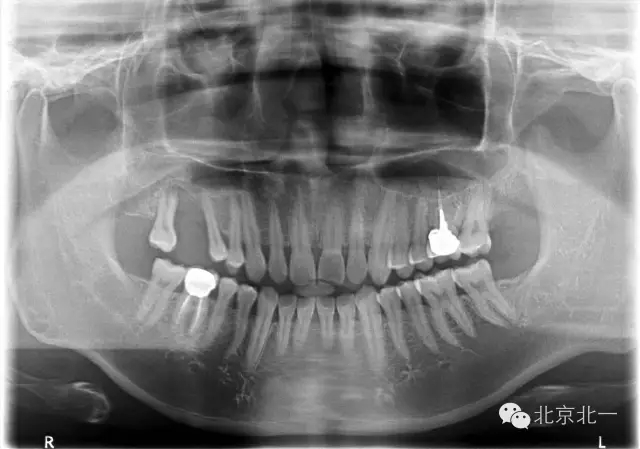

患者,男,30歲,右側(cè)上頜后牙區(qū)缺失,咨詢種植。

檢查:15、16 缺失。17三度松動。

CBCT顯示,骨寬度可,骨高度不足,月3mm。頜間距離增大。

診斷:牙列缺損,牙周炎

圖二:手術(shù)前全景片